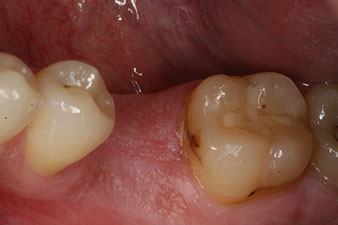

A 28-year-old patient with a history of heavy smoking had to have tooth 36 extracted as a result of recurring apical periodontitis.

Due to the generally intact neighbouring teeth the only way to fill the gap was an implant.